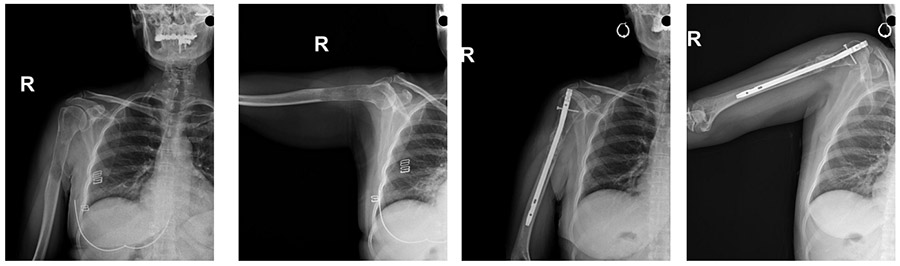

Ameliyat Öncesi: Röntgende ilk başvuru anında proksimal humerus yerleşimli sınırları belirsiz litik lezyon ve ilk ameliyat sonrası greft ve intramedüller çivi uygulanımı görülmekte

Ameliyat Sonrası: Röntgende rezeksiyon sonrası distalde geri kazanılan kemiğin anatomik plak ile fiksasyonu ve çimentolu proksimal humerus tümör protezi uygulanımı görülmekte